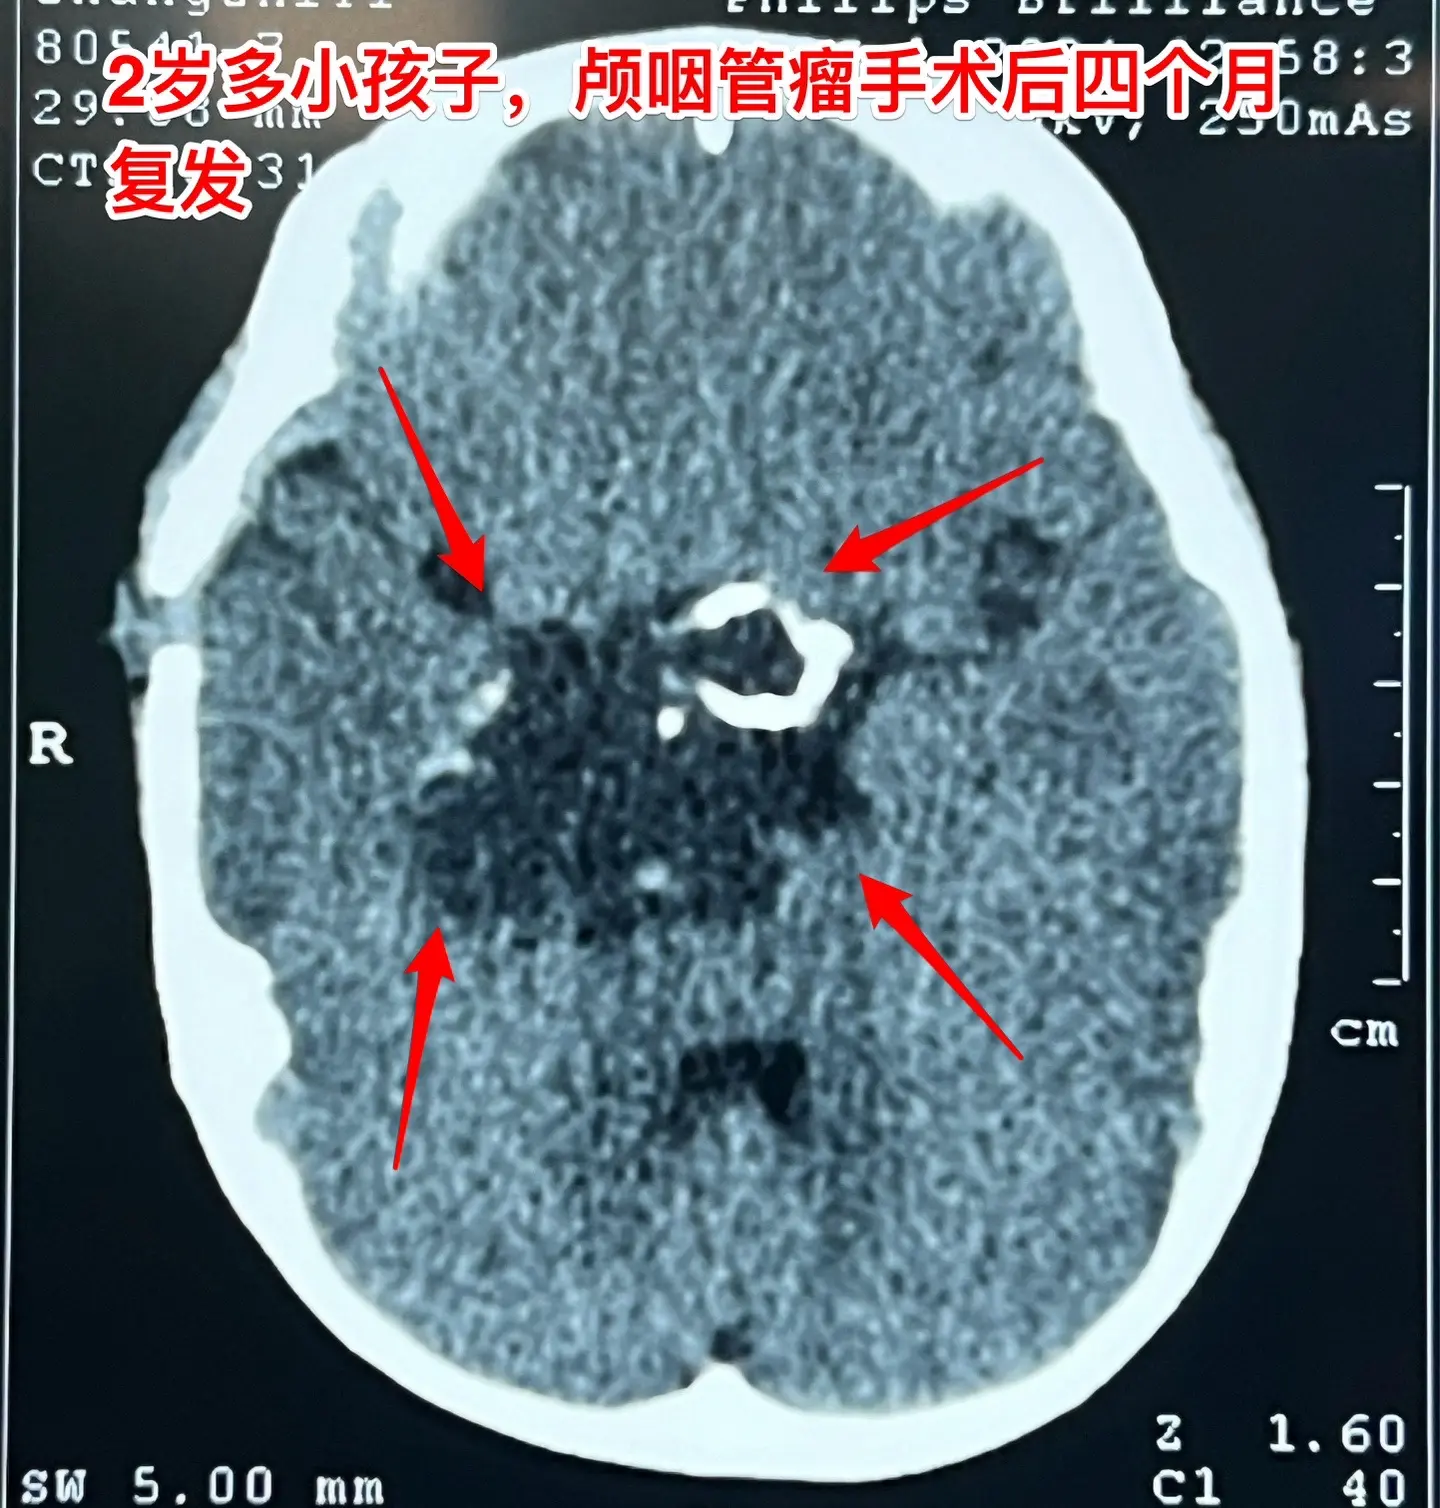

2岁孩子颅咽管瘤复发不得不接受手术。2岁多的山东女孩子,在颅咽管瘤手术...

2024-08-11 14:28

警惕小儿脑肿瘤。小孩子如果长了鞍区肿瘤,一般都会出现症状,一旦有了症状...